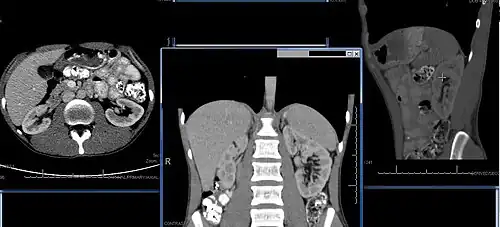

Chronic kidney disease (CKD) has been recognized as a leading public health problem worldwide. The global estimated prevalence of CKD is 13.4%, and patients with kidney failure needing renal replacement therapy are estimated between 5 and 7 million.[6] Procedures used in the management of kidney disease include chemical and microscopic examination of the urine (urinalysis), measurement of kidney function by calculating the estimated glomerular filtration rate (eGFR) using the serum creatinine; and kidney biopsy and CT scan to evaluate for abnormal anatomy. Dialysis and kidney transplantation are used to treat kidney failure; one (or both sequentially) of these are almost always used when renal function drops below 15%. Nephrectomy is frequently used to cure renal cell carcinoma.

Imaging

Renal ultrasonography is essential in the diagnosis and management of kidney-related diseases.[48] Other modalities, such as CT and MRI, should always be considered as supplementary imaging modalities in the assessment of renal disease.[48]